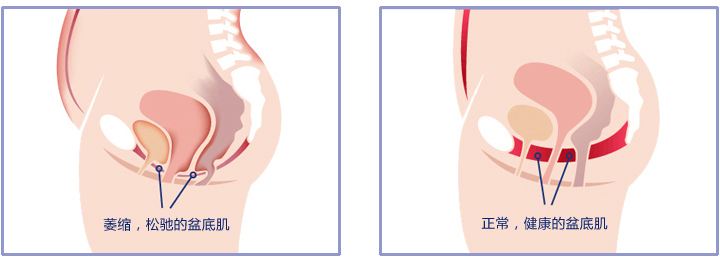

1、年龄。随着年龄增长,女性尿失禁患病率逐渐增高,高发年龄为45~55岁。年龄与尿失禁的相关性可能与随着年龄的增长而出现的盆底松弛、雌激素减少和尿道括约肌退行性变等有关。一些老年常见疾病,如慢性肺部疾患、糖尿病等,也可促进尿失禁进展。

3、盆腔脏器脱垂。压力性尿失禁和盆腔脏器脱垂紧密相关,二者常伴随存在。盆腔脏器脱垂患者盆底支持组织平滑肌纤维变细、排列紊乱、结缔组织纤维化和肌纤维萎缩可能与压力性尿失禁的发生有关。